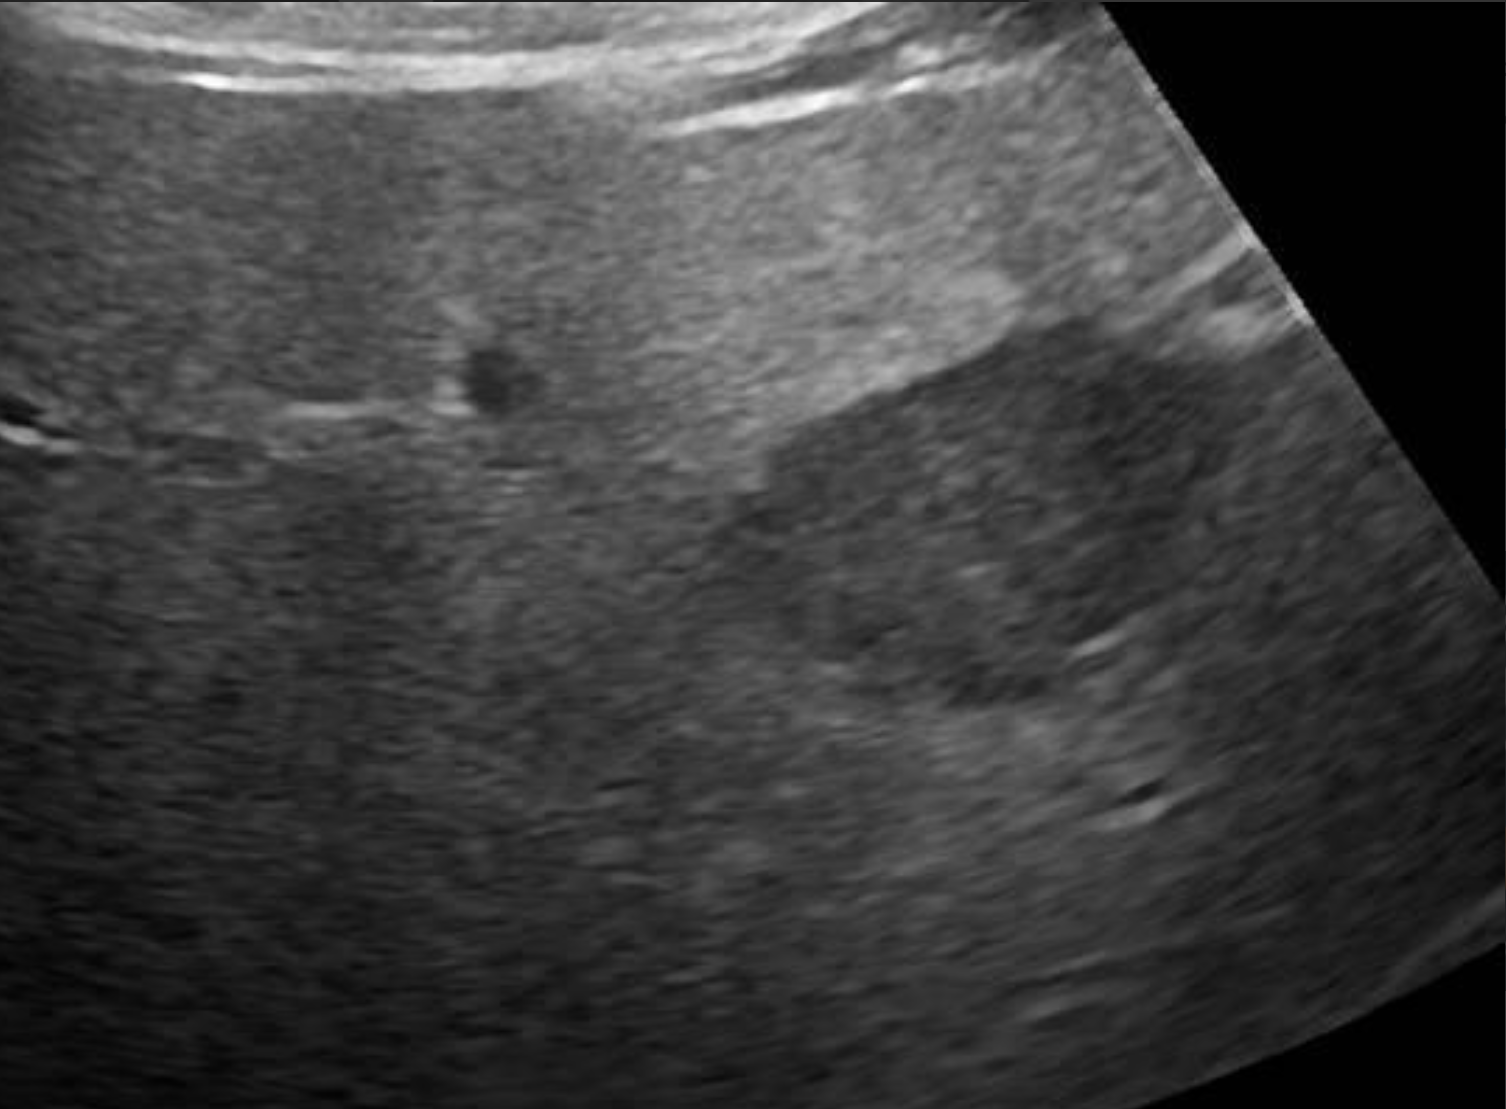

Which of these liver masses/nodules is a malignant tumor.

B-mode ultrasonography is highly sensitive for detecting focal liver lesions but is poorly specific for lesion type. Hepatic masses may appear:

• Hypoechoic, hyperechoic, or mixed echogenicity

• Well-marginated or irregular

• Solitary or multifocal

Importantly, echogenicity does not correlate reliably with malignancy. Multiple studies have demonstrated substantial overlap in the sonographic appearance of benign nodules, primary hepatic tumors, and metastatic lesions (Nyland et al., 2002; O’Brien et al., 2004)

In a large retrospective study of canine liver tumors, no consistent B-mode ultrasonographic features reliably differentiated hepatocellular carcinoma, cholangiocarcinoma, sarcoma, or metastatic lesions, aside from lesion distribution (O’Brien et al., 2004). Hepatocellular carcinomas were more likely to be solitary, whereas sarcomas and metastases were more often multifocal, but significant overlap existed.